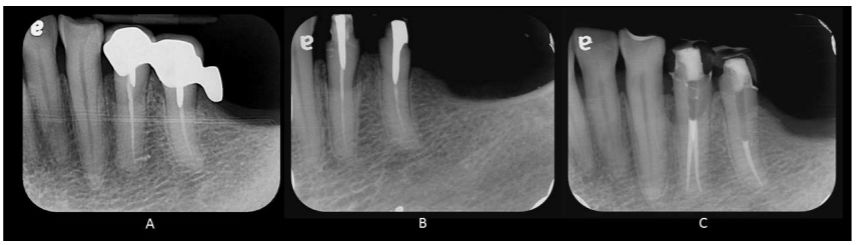

5.左下顎第一與第二小臼齒需要根管再治療(圖A),圖B以X光平行儀(cone indicator)正角度照射(facial projection),圖A與圖C為近心側往遠心側照射 (mesial projection),則左下顎第一小臼齒於根管再治療前遺 漏了那一個根管? (A)頰側根管(buccal canal) (B)舌側根管(lingual canal) (C)近心側根管(mesial canal) (D)遠心側根管(distal canal)